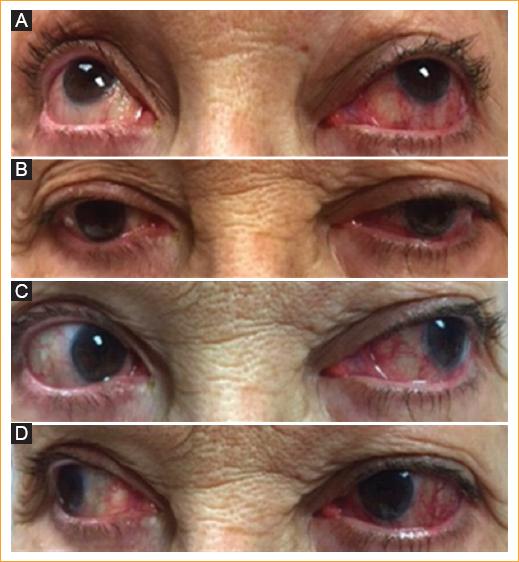

Mujer de 64 años que acude a la consulta porque «Tengo salido el ojo izquierdo y veo doble». Inicia hace 7 meses con sensación súbita de masa y presión en el ojo izquierdo, ardor, dolor, diplopía y edema bipalpebral. Niega antecedentes de trauma. Fue tratada en múltiples ocasiones con esteroides, sin mejoría. En la revisión por sistemas refiere cefalea crónica. Al examen oftalmológico se encuentra una agudeza visual normal bilateral, anisocoria y defecto pupilar aferente en el ojo izquierdo. En el test de saturación al rojo se observa desaturación al rojo del 40% en el lado izquierdo. Motilidad ocular de ojo izquierdo con hipofunción del recto lateral de –4 (Fig. 1). Proptosis leve en el ojo izquierdo a la exoftalmometría. La biomicroscopía del ojo izquierdo muestra una marcada ingurgitación vascular nasal y temporal. La presión intraocular y la refracción son normales en ambos ojos. Al fondo de ojo se observan vasos tortuosos en la arcada temporal superior izquierda (Fig. 2).

Figura 1 Examen clínico de la motilidad ocular. A: supraversión. B: infraversión. C: levoversión con marcada hipofunción del recto lateral. D: dextroversión.